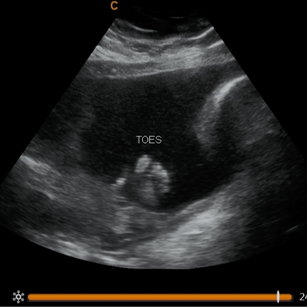

Movements: Strong kicks and rolls, practicing muscle control.